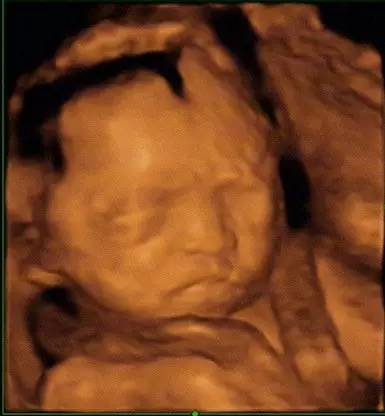

你有沒有好奇過肚子里寶寶的模樣?有沒有想看看他在你肚子里怎么打發時間呢?他有沒有在吃手,有沒有打哈欠,有沒有“練武術”?四維超聲可以讓你清清楚楚看到這一切。

“小金人”在超大顯示屏上躍然出現。好動的小家伙,像是一個體操運動員。老公說像是孫悟空,手舞足蹈就像12周時候一樣。醫生選了幾個畫面留下影像,有一幅寶貝閉著眼睛露出小臉的樣子。大家說像我的地方是他的大腦門。寶貝你一定要揀我們的優點吸收呀。我們沒有的優點,你也要想辦法原創啊!

這就是四維的樂趣,直觀的圖像給外行人帶來的是幸福激動的體驗。一家人邊聊邊看肚子里寶寶的各種萌態,隔時空相見的感覺就是這么贊!